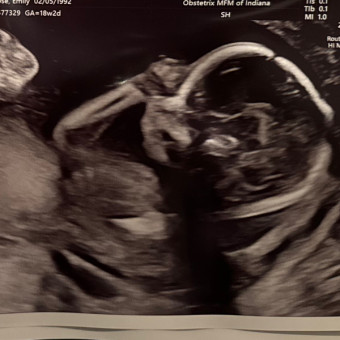

Baby Michael

Emily & Michael Rose

South Bend, IN

December 4, 2024